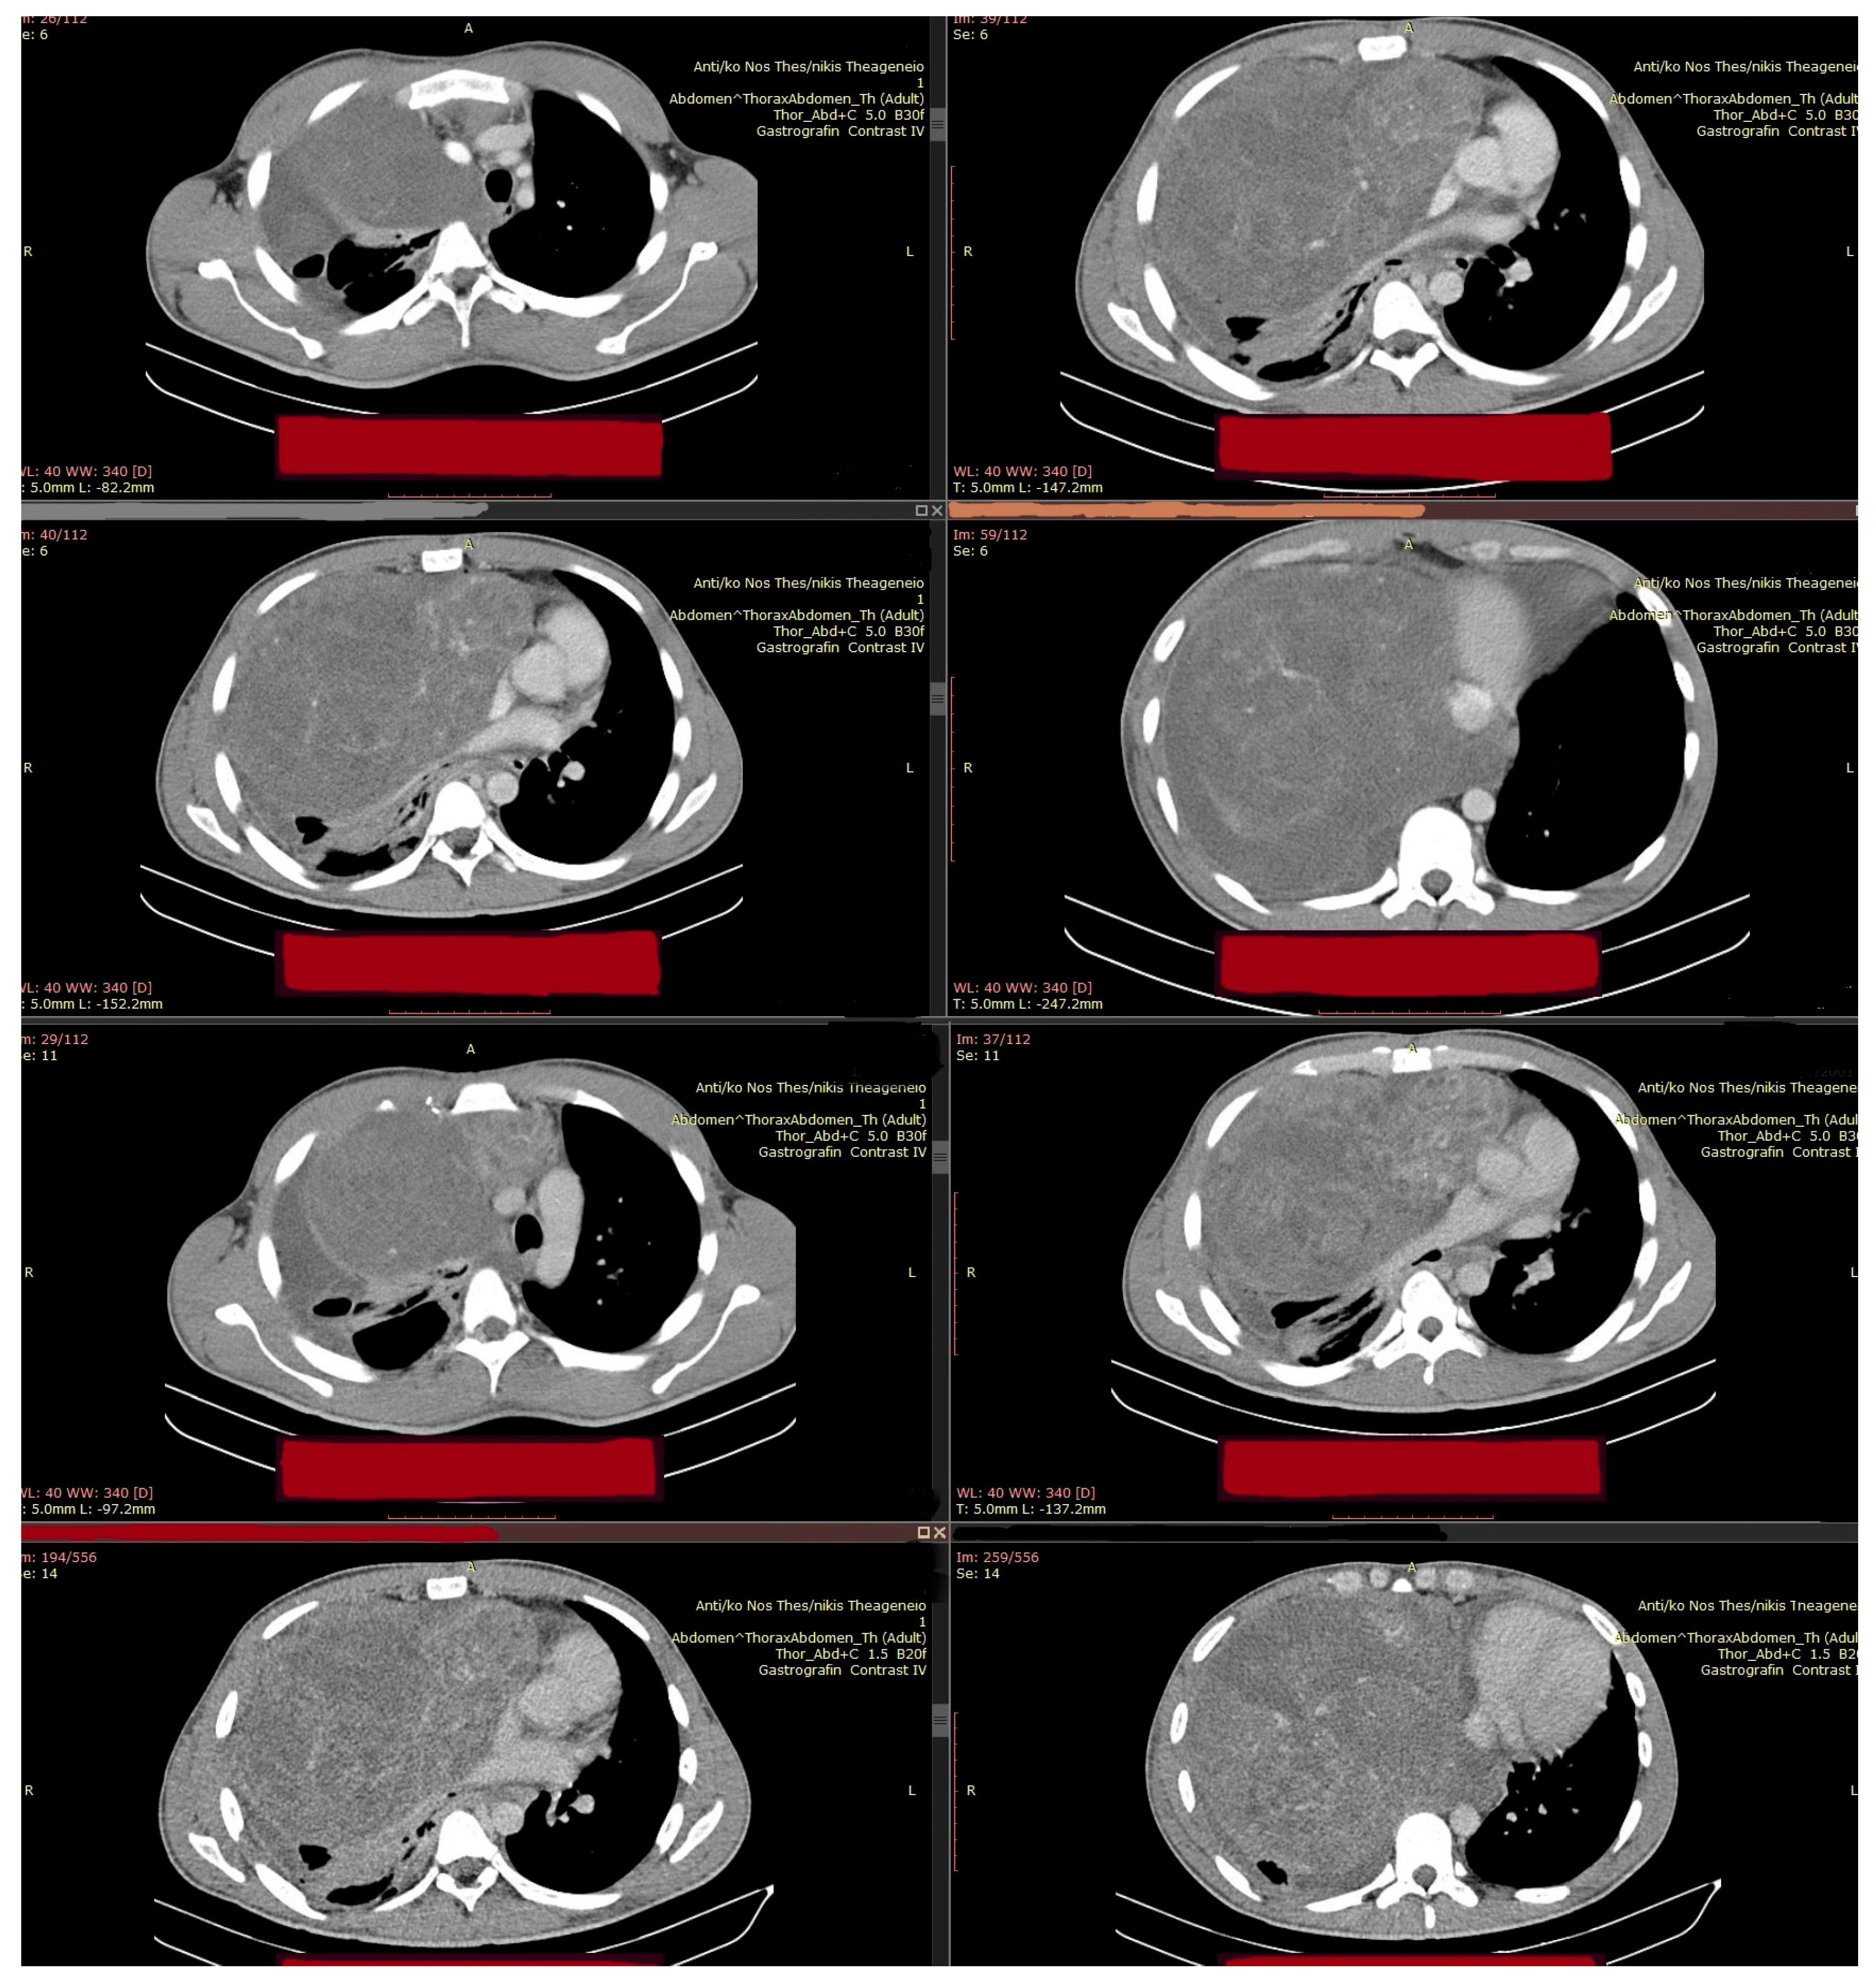

Thus, the scheme was modified to VIP-Regimen, specifically, Cisplatin® (20 mg/m2 i.v. on days 1–5) Etoposide® (75 mg/m2 i.v. on days 1–5), and Ifosfamide® (Sanofi Hellas, Athens, Greece) (1200 mg/m2 i.v. on days 1–5), with the additional application of Mesna® (Baxter Hellas, Athens, Greece; IFET, Rome, Italy) (120 mg/m2 i.v. on day 1 and continuously 1200 mg/m2 i.v. on days 1–5) (Table 2) [14]. This is an alternative chemotherapeutic choice, used particularly in cases of poor prognosis or platinum-refractory disease, to avoid additional pulmonary toxicity. VIP-Regimen is always administered under close monitoring due to the increased eventual hematologic toxicity. During therapy, the patient developed febrile neutropenia, necessitating dose adjustments, the administration of G-CSFs, and inpatient supportive care. Further imaging controls indicated that the mass continued to significantly increase (DMax: 28 cm × 25 cm × 13 cm), with severe localized pressure effects on neighboring cardiopulmonary and vascular structures.

During this second line of chemotherapy, the progressive worsening of the patient’s clinical condition necessitated a third surgical intervention, focused primarily on “life-saving” requirements and current life-threatening indications [15] (Figure 6). The evolution of residual disease, following chemotherapy, demanded emergency surgical intervention, requiring radical resection, especially given the presence of teratoma and suspected chemoresistant elements on imaging. According to published reports and case series (e.g., Bokemeyer et al. [16], 2002; Kessler et al., 2004 [17]), post-chemotherapy resection is critical in achieving cure in patients with residual mediastinal masses, as viable teratoma or transformed malignancy may persist despite radiologic response. In contrast to upfront surgery, which might have been incomplete or hazardous due to the tumor bulk and vascular proximity, a successful radical resection would also provide a more definitive pathological assessment, confirming that preoperative biopsy and imaging may significantly underestimate tumor complexity.

Figure 6. Preoperative (pro median sternotomy, extended with complementary “T-Shaped” mini anterior (R) thoracotomy) Chest-CT.